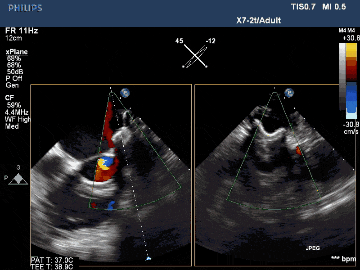

該例患者為男性58歲,陣發(fā)性房顫,9個月前突發(fā)急性腦梗死,3月前曾行房顫射頻消融術(shù)。2023年11月經(jīng)胸超聲心動圖示左房內(nèi)徑46mm,經(jīng)食道超聲心動圖示左心房及左心耳內(nèi)未見血栓形成,CHA2DS2-VASc評分3分,HAS-BLED評分2分。DSA測得左心耳開口直徑約23mm,錨定區(qū)域約18mm。

術(shù)后TEE影像示封堵完全